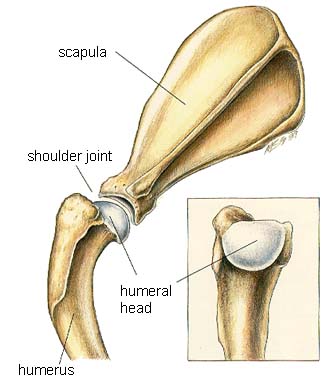

The musculoskeletal system includes all the muscles, bones and joints.

- Shoulder

Shoulder